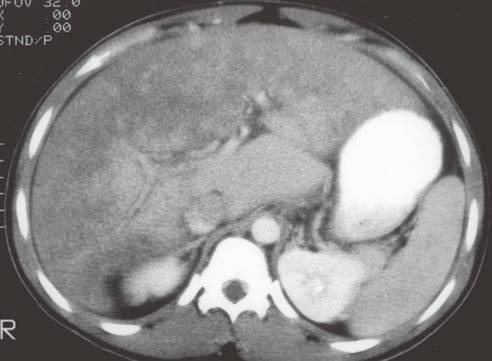

| 布加综合征(图4 和图 5) | 肝脏体积增大,密度弥漫性减低(由肝实质充血造成)。 | 在肝内静脉、肝静脉或下腔静脉肝上段流出道梗阻。少见,与髙凝状态、口服避孕药、怀孕、浸润性肿瘤和先天性瓣膜有关,“翻转”式对比增强(见图5)。 |

| 肝淤血(图6) | 肝脏体积增大伴弥漫性密度减低。 | 见于充血性心力衰竭或缩窄性心包炎。尽管中心静脉压升高而导致下腔静脉和肝静脉明显扩张(不同于布加综合征,肝静脉和变细的下腔静脉不显影),但强化形式与布加综合征相似。 |

图4布加综合征

图5布加综合征